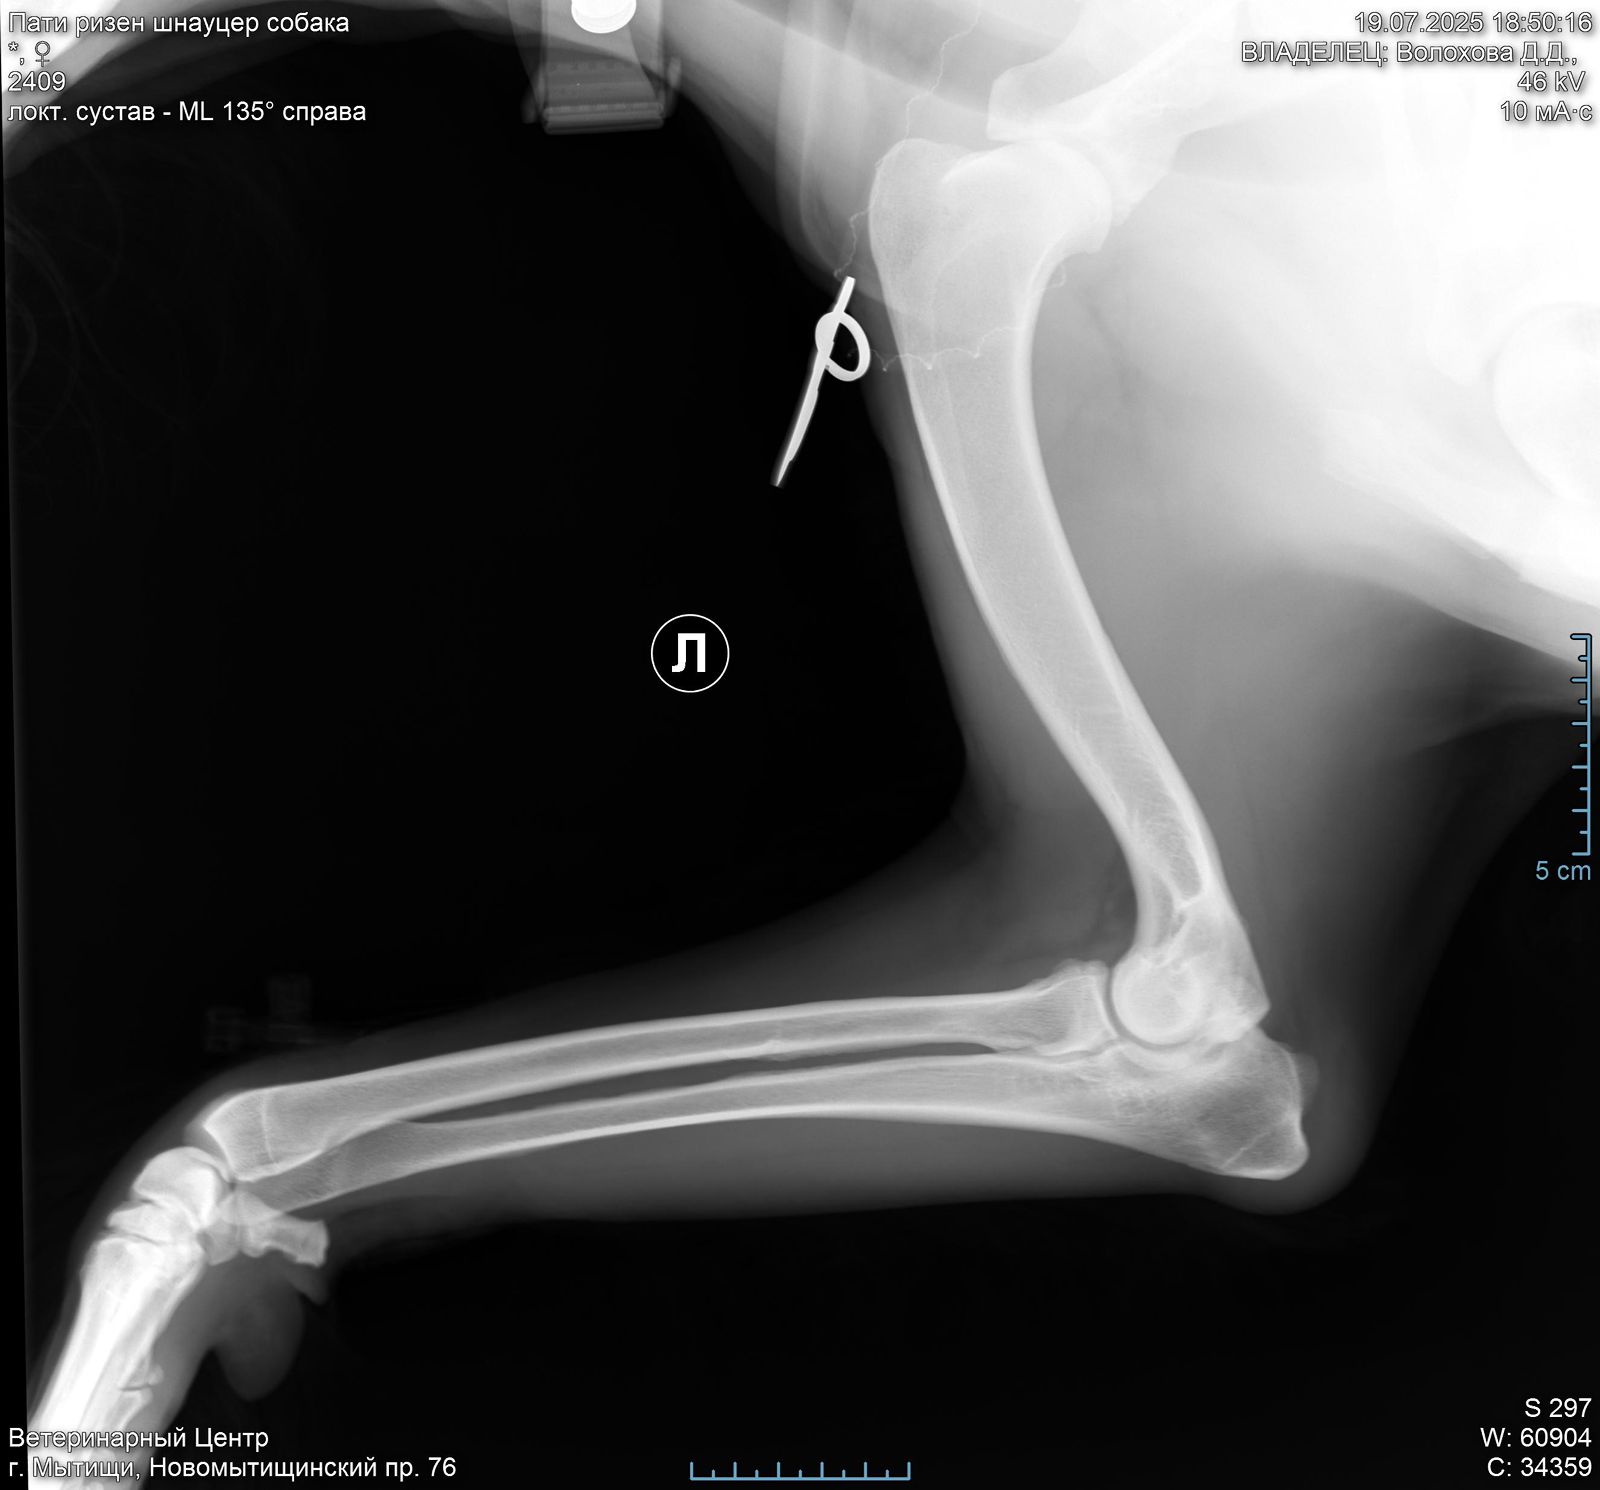

В правом локтевом суставе у Пати болтается 2 осколка кости( от мыщелков).

Их надо убирать.

Проблема не приобретенная у нас, а врожденная или травма в прошлой жизни.

Операция сложная, и делается 2 способами: на открытом суставе или через артроскоп ( если осколки меньше 1 см).

Поэтому вначале требуется КТ, чтоб понимать, какой метод в нашем случае актуален.

Есть шансы поиметь осложнения при обоих. У каждого есть плюсы и минусы.

Но пока есть шанс убрать осколки и жить вполне обычной жизнью ( не спортивной, но и не инвалид).

Артроз сустава никуда не исчезнет, но если повезет, и сильно прогрессировать не будет.

При таком поражении сустава удивительно, что нет выраженной хромоты.

Левый локтевой пока под вопросом, есть там проблемы или нет. КТ покажет.